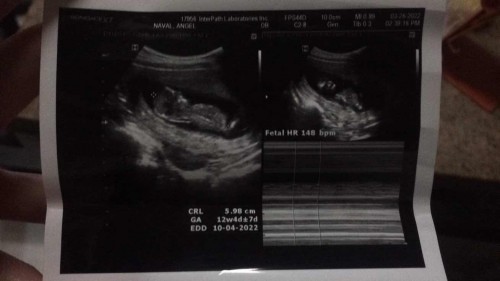

Hello good evening, ask ko lang po sainyo kung yung nakalagay po sa ultrasound nyo kung ilang weeks pregnant exact po sa date ng huli nyong regla? Sakin po kasi dec 9 last mens ko spotting na brown nag search po ako nakalagay Early sign of pregnancy. Tapos nung ultrasound ko na 12 weeks lang pala pero pag count base sa huling mens 15 weeks na. Ano po kaya tama? 15 or 12? 2 times na po ako nag ultrasound 12weeks nakalagay. Irregular po mens ko... kung 12 weeks po ako ngayun dec 30 po ako nabuntis???? Sana po ma help nyo ako mga mommies 🥰🥰🥰

irregular ako kamamsh so nagbase kami sa TVS Sept baby ko..kaw October so baka nagDo and nagcreate baby niu almost katapusan ng December or 1st week January..maniwala ka sa Due date binigay sau ng Ob kasi sila nakakita gaano kalaki baby mo and gaano kabilis heart beat nia

Irregular ka kasi sis eh. Posible kasi nag ovulate ka later than you expected. Pag irregular kasi ang pinagbabasehan talaga is ung ultrasound. As long as wala naman signs na me problema sa ultrasound. I wouldn’t worry. Basta healthy si baby at me heartbeat un ang important.

12weeks po , nakapag second choice kana po so meaning 12weeks po. Irregular po kasi kayo kya gnyn. ok lng po yan kung 15weeks or 12weeks ang importante malusog kau ni baby

hindi po sya tutugma .. kung ano po ang expected dd nyo yon po ang sundin nyo.. ung sa ultrasound po. gnyan din po ako. :)

Alam ko mommy sa ultrasound tayo babase ng bilang kase yan din ang sususndin ng ibang ob.

yung pinaka first tvs mo mamshie dun magb base ang OB :) congratulations sa blessing ❤️